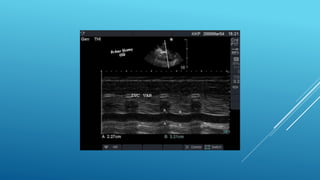

โ€ข Tricuspid annular plane systolic excursion

โ€ข TAPSE of <17 mm indicates RV dysfunction